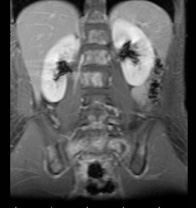

[单选题]7岁,男,发热、消瘦,数月前触及颈部淋巴结肿大,CT和MR检查如图,请选择最可能的诊断()A.淋巴瘤B.结节病C.淋巴结核D.转移性淋巴肿大E.胸腺瘤

[单选题]女,32岁,发热、消瘦,数月前触及颈部淋巴结肿大,CT和MR检查如图,最可能的诊断是()A .淋巴瘤B .结节病C .淋巴结核D .转移性淋巴肿大E .胸腺瘤